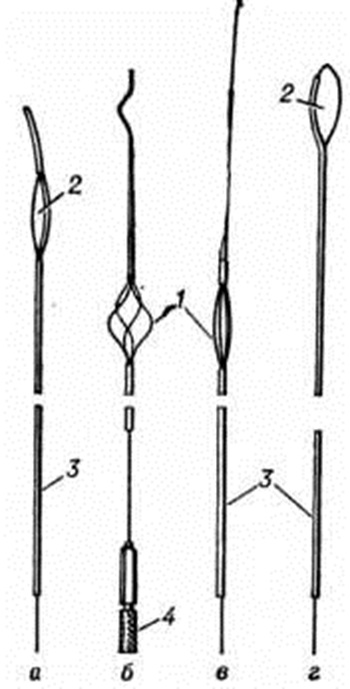

При отсутствии эффекта от медикаментозного лечения и физиотерапии и остром нарушении оттока мочи может быть применена эндовезикальная уретеролитоэкстракция, для которой предложено несколько экстракторов — Джонсона, Дормиа, Пашковского, Цейсса (рисунок 8) и другие Составными частями их являются катетер, проводник и захватывающее устройство (петля, корзина), в некоторых из них имеются приспособления для управления экстрактором и фиксации камня в корзине.

Основными показаниями к уретеролитоэкстракции служат камни нижнего отдела мочеточника небольших размеров (до 0,8 сантиметров), отсутствие признаков периуретерита, сохранение удовлетворительного тонуса мочеточника.

Противопоказания к низведению камней мочеточника — острый пиелонефрит, пионефроз, гидронефроз, анурия, уросепсис, стриктура, воспалительные заболевания уретры и другие У мужчин уретеролитоэкстракцию следует применять крайне осторожно из-за возможности развития острого простатита, уретроррагии и других осложнений.

Уретеролитоэкстракцию производят в стационаре. Больной должен быть обследован полностью в связи с возможностью экстренной операции. Перед экстракцией камня больному назначают спазмолитические и обезболивающие средства (платифиллин, атропин, промедол и другие), производят рентгенографию мочевых путей. После применения различных методов обезболивания, включая наркоз, экстрактор вводят в мочеточник через цистоскоп таким образом, чтобы петля или корзинка его была проведена в закрытом виде выше камня. Затем раскрывают корзинку экстрактора и низводят его. При этом одновременно выполняют лёгкие вращательные движения, пытаясь захватить камень и извлечь его. В тех случаях, когда камень из мочеточника вывести невозможно, экстрактор оставляют в состоянии натяжения, которого достигают с помощью подвешивания груза до 200 грамм (через блок) на срок 1—4 суток до отхождения камня. Одновременно применяют антибактериальные и спазмолитические препараты. После извлечения камня рекомендуются катетеризация мочеточника в течение 2—3 дней и противовоспалительное лечение.

Основные осложнения уретеролитоэкстракции могут быть технического, травматического и воспалительного характера (отрыв, «перелом» экстрактора, ущемление камня, обострение пиелонефрита, перфорация стенки мочеточника и другие). При невозможности экстракции камня применяют уретеролитотомию.